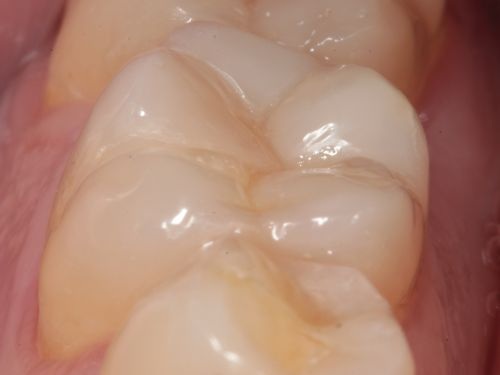

A 35-year-old male presented to the clinic to replace some inadequate restorations, one of which was for the lower right first molar (Fig. 1). For this tooth, the molar was restored with composite resin using the direct technique. The operative field was isolated, the old restoration was removed, and surface hybridization was completed using Futurabond U universal adhesive from Voco (Fig. 2). After placing a sectional matrix and a spacer ring, the composite resin (Voco’s GrandioSO 4U, shade A2) was placed in the proximal box with a thickness less than 4 mm, which is the maximum recommended thickness for the chosen material (Fig. 3). Additional increments of composite resin were applied to complete the anatomical stratification. The final morphology was sculpted, followed by light-curing to ensure complete polymerization (Fig. 4). The rubber dam was removed (Fig. 5), and the occlusion was adjusted using a finishing carbide bur with 12 blades (Fig. 6). Finishing and polishing was completed, with the final result shown in the Figures 7 and 8.

Fig. 1